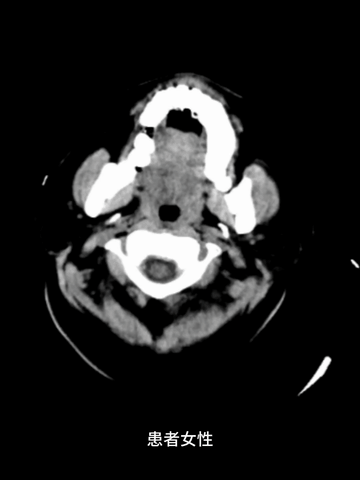

女,42岁

症状:突发左侧肢体麻木乏力

急诊多模式CT

CT平扫:ASPECT是9分,薄层MIP重建于右ICA末端至M2近端见长段血栓高密度影。

颅脑4D-CTA和颈部CTA示:右ICA末端至MCA M2近端长段闭塞,3型弓。

CTP:右MCA区大范围TTP显著延长,CBV和CBF仅在基底节区见小范围核心梗死征象。